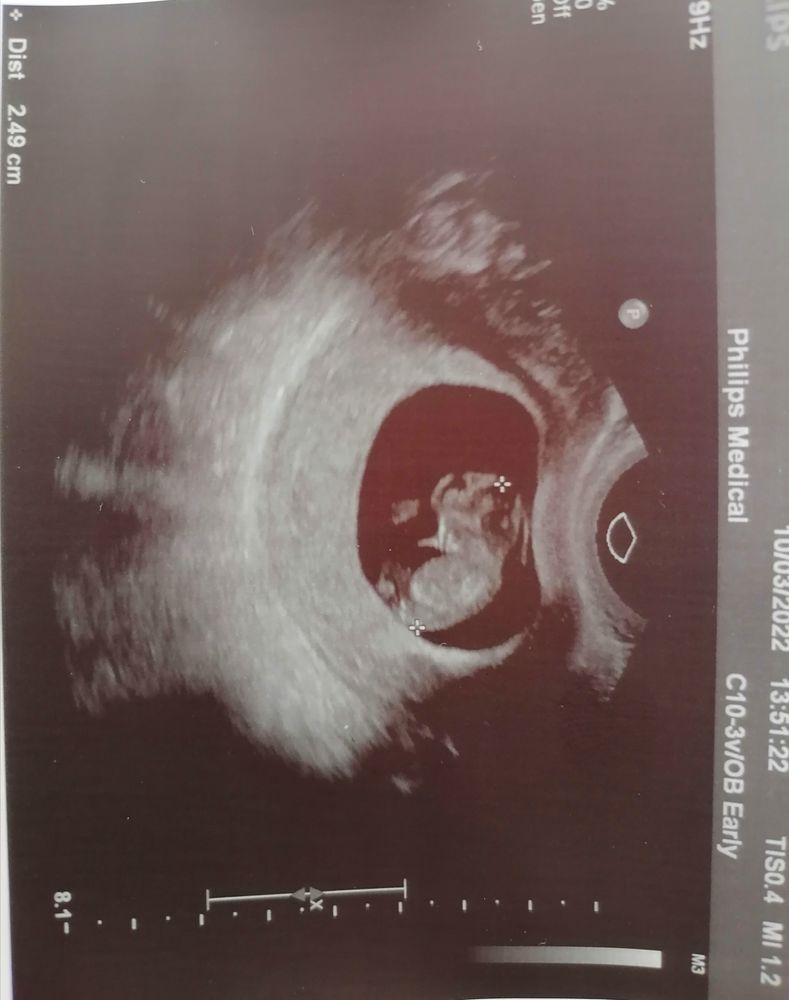

Первое фото малыша на узи 9 недель

Результаты: УЗИ, КТГ, доплера, скринингаДевочки, пришла с узи, успокоили, дали фотографию малыша )))

А с малышом все хорошо. Сердечко в норме, бьётся ровно, помахал мне ручками, прикрепился к задней стенке.